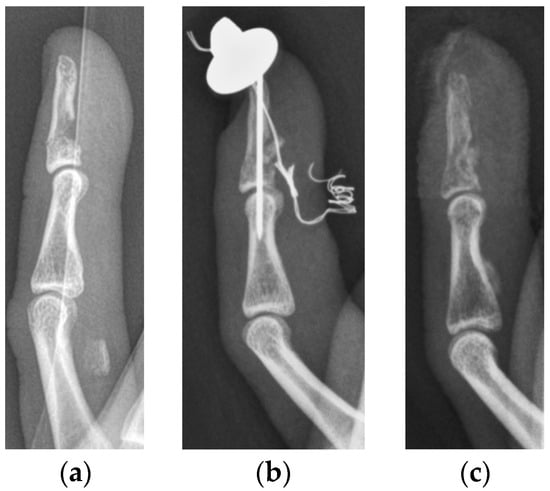

Jersey finger type V was described by Al-Quattan in 2001 [6]. He defined it as an FDP tendon avulsion with a concurrent transverse fracture of the distal phalanx, resulting in an extraarticular (type Va) or an intraarticular avulsion fracture (type Vb) (Figure 1). This type of jersey finger is deemed to be the least frequent. In the literature, only case reports or case series with a maximum of four patients can be found [7,8,9]. In many cases, they are not even classified as jersey finger type V, which indicates the controversial understanding of this injury [10,11].

Figure 1. Schematic illustration of jersey finger type Va (a) and type Vb (b) injuries.

Figure 2. Lateral radiographs of a minimally displaced type Va (a) and type Vb (b) jersey finger, treated conservatively in our department.